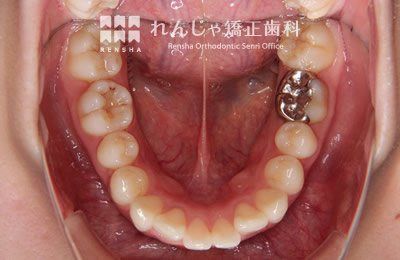

右下7番目(12歳臼歯)がなかなか出てこないため、6歳臼歯を支えに引っ張り出しました。

治療前

→

治療中

治療後

| 主訴 | 前歯のがたつき |

|---|---|

| 診断名 | Angle Class I 叢生 |

| 初診時年齢 | 10歳10か月 |

| 装置名 | 舌側弧線装置 |

| 抜歯非抜歯 | 非抜歯 |

| 治療期間 | 3年10か月 |

| 費用の目安 | 約36万円+消費税(検査料金、都度の処置費用等も合わせた総額) |

| リスク副作用 | 歯の移動に伴う軽微な歯根吸収、歯槽骨吸収、歯肉退縮(いずれも本症例ではほぼ無し)、矯正器具装着中のカリエスリスク増大(本症例ではカリエス発生無し) |